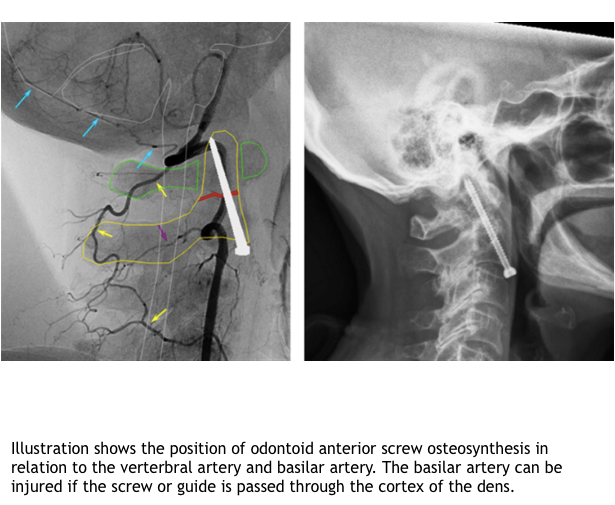

Decribe the technique for anterior odontoid screw osteosynthesis?

What are the complcaitions of axis fx?